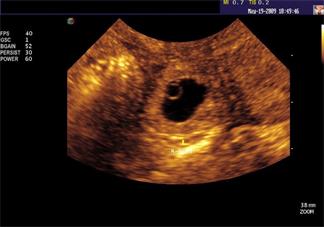

懷孕后hcg正常值是多少 孕期hcg可以檢查出宮外孕嗎

懷孕以后,受不同階段的影響,女性hcg的數值也存在不同的變化,而且和孕酮以及流產之間存在一定的關系,對于hcg是孕

孕檢HCG偏高會是宮外孕嗎 有宮外孕怎么辦

血HCG是孕檢中非常重要的一個項目,可以推測是否懷孕以及胎兒異常,孕檢HCG偏高會是宮外孕嗎?有宮外孕怎么辦?接下

孕檢hCG升高是宮外孕嗎 假性低水平hCG 升高是什么

在孕檢的時候最怕指標出現異樣,很多的人看不懂孕期檢查的各項指標,醫生只是說了具體的問題,自己不知道原因是什